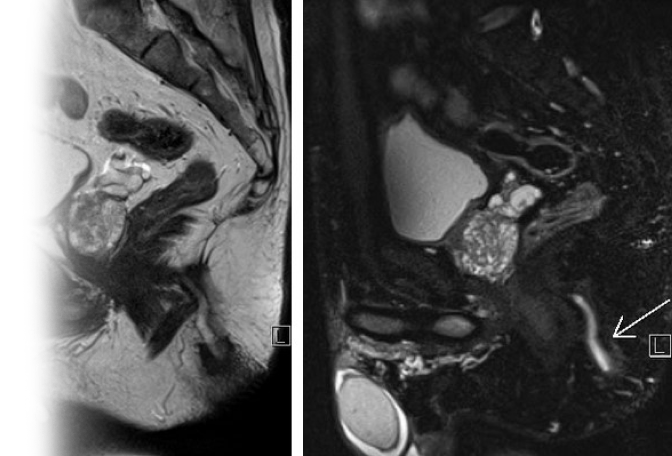

Магнитно-резонансная томография предстательной железы с динамическим контрастированием – важный метод исследования с введением контрастного вещества.

Данный метод позволяет визуализировать предстательную железу и семенные пузырьки до и после контрастирования.